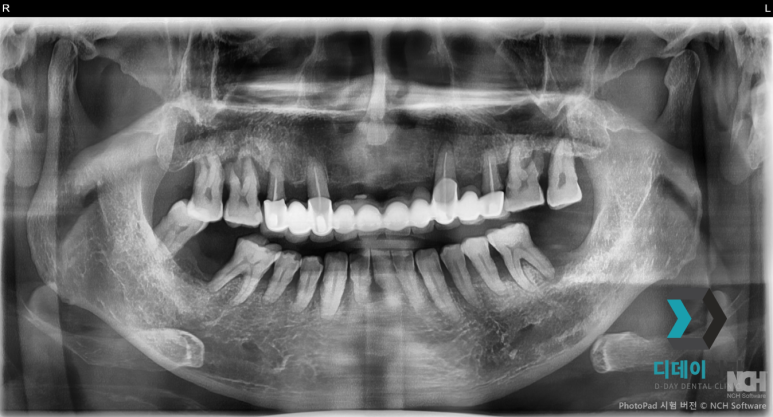

양쪽 위아래 심한 치주염으로 발치 후 즉시 임플란트 식립